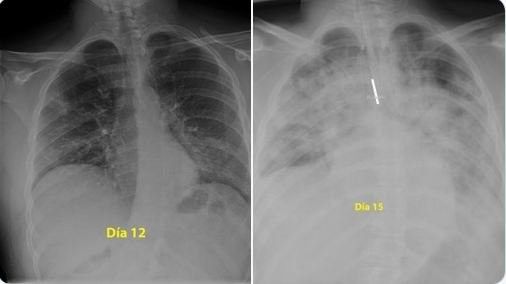

Për ata që j besojnë se nuk preken dhe vazhdojnë të dalin në park pa zbatuar urdhrat e vendosur për të ndjekur në shtëpi, ju ftojmë të shikoni mushkëritë e një djali 28-vjeçar të para me rreze X. Mushkërit janë të zeza ndërsa e bardhë është pneumonia ose lëngu i infeksionit që më pas bllokon frymëmarrjen. Pamjet janë publikuar nga një mjek në Spanjë i quajtur Donni.

Agravimi i virusit është shumë i shpejtë dhe nga dita e 12 në të 15 shihet se mushëkëritë e pacientit janë mbushur plotë me lëngun e infeksionit. /tch/